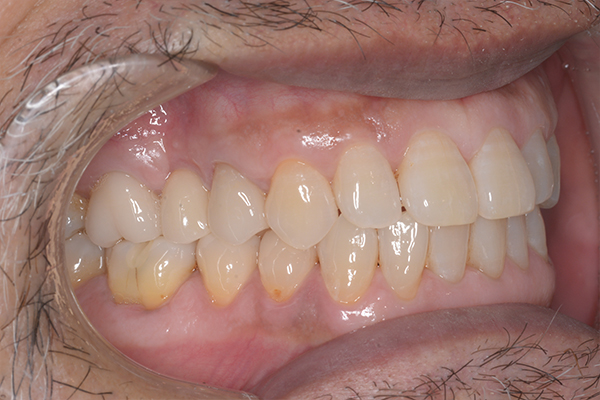

治療前〜治療後のレントゲン写真

患者様の要望過去に治療したブリッジを外し咬み合わせの平面を整えて、被せ物や詰め物を綺麗にしたい。

治療期間10ヶ月

治療費用1,600,000円

治療内容インプラント2本、アンカースクリューを用いた部分矯正、

セラミックによる補綴治療

治療のリスクセラミックの破折の可能性